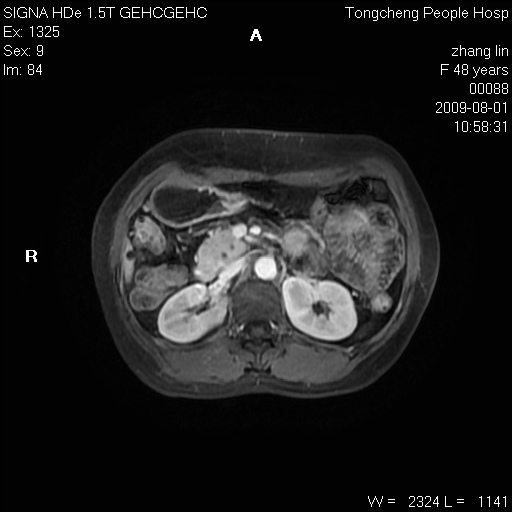

女,48岁。健康体检,彩超发现右肾占位性病变。平素健康。

临床诊断:右肾占位性病变,性质待定(囊肿?肿瘤?)。

上中腹部mr平扫+增强扫描,图像如下:

右肾上极见一类圆形病灶,t1wi呈等信号t2wi呈等高混杂信号,三期增强无强化,边界清---考虑囊肿出血。

同反相位均表现为等信号,病变无强化,考虑含蛋白的囊肿可能,弥散加权相或许有些帮助,

肝囊肿

慢性胆囊炎